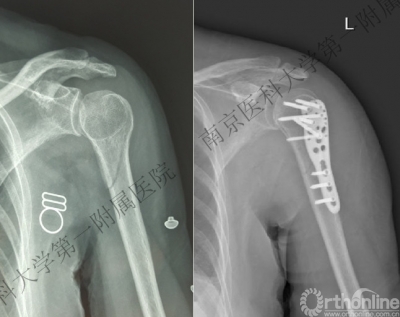

男性,48岁,坠落伤致左肩关节肿痛、活动受限1天。

术后肩关节X线正位片

七、治疗原则

首选手术治疗:

- 恢复正常盂肱关节关系。

- 修复塌陷的肱骨头(长期塌陷部位会因松质骨吸收而仅遗留软骨壳)。

- 稳定肱骨近端骨折。